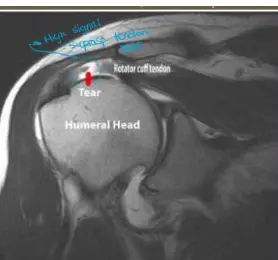

Q21 - What causes pain during overhead activities when MRI shows rotator cuff muscle tear?

- Subscapularis and infraspinatus muscle tears

- Note: Supraspinatus was not included in the answer choices

Question 56 - A 45-year-old male with anterior shoulder dislocation. Which injury is demonstrated in the attached MRI?

- d. Supraspinatus tear

Rotator Cuff Pathology

- Common cause of shoulder pain during overhead activities

- May involve tears in subscapularis, infraspinatus, or supraspinatus muscles

- Diagnosis confirmed with MRI imaging

Question: A case scenario that was suggestive of an anterior shoulder dislocation in a 45-year-old male. Which of the following injuries is demonstrated in the attached MRI?

- Answer: Supraspinatus tear